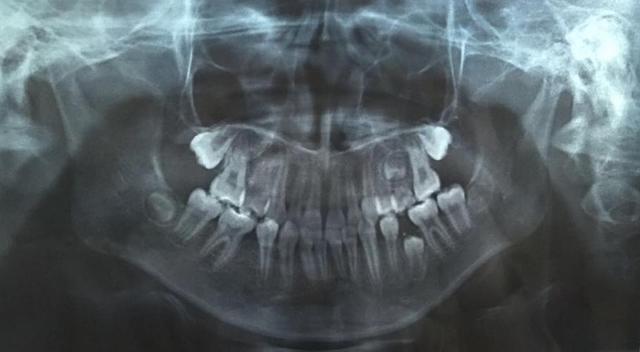

文章插图

图片由院方提供

儿童口腔科副主任医师王锐副教授为琦琦拍摄了一张曲面断层片 , 发现琦琦左下后牙区有一颗牙齿因间隙不足阻生 , 建议家长接受矫正治疗 , 扩开间隙 , 观察阻生于颌骨内的牙齿是否可以顺利萌出 。 治疗过程相对复杂 , 治疗周期较长 , 需要每隔一个月复诊一次 。 “孩子今年上初中 , 课业压力越来越大 , 但既然牙齿出现这么严重的问题 , 挤时间也要积极配合医生治疗 。 ”面对这种情况 , 琦琦妈妈无奈的说 。

据王锐副教授介绍 , 孩子的乳牙脱落要及时到医院拍摄曲面断层片观察是否存在乳牙早失、恒牙阻生或发育异常等情况 , 一旦发现乳牙早失必须及时制作间隙保持器保留牙齿间隙 , 给恒牙足够的萌出空间 , 避免严重后果 。